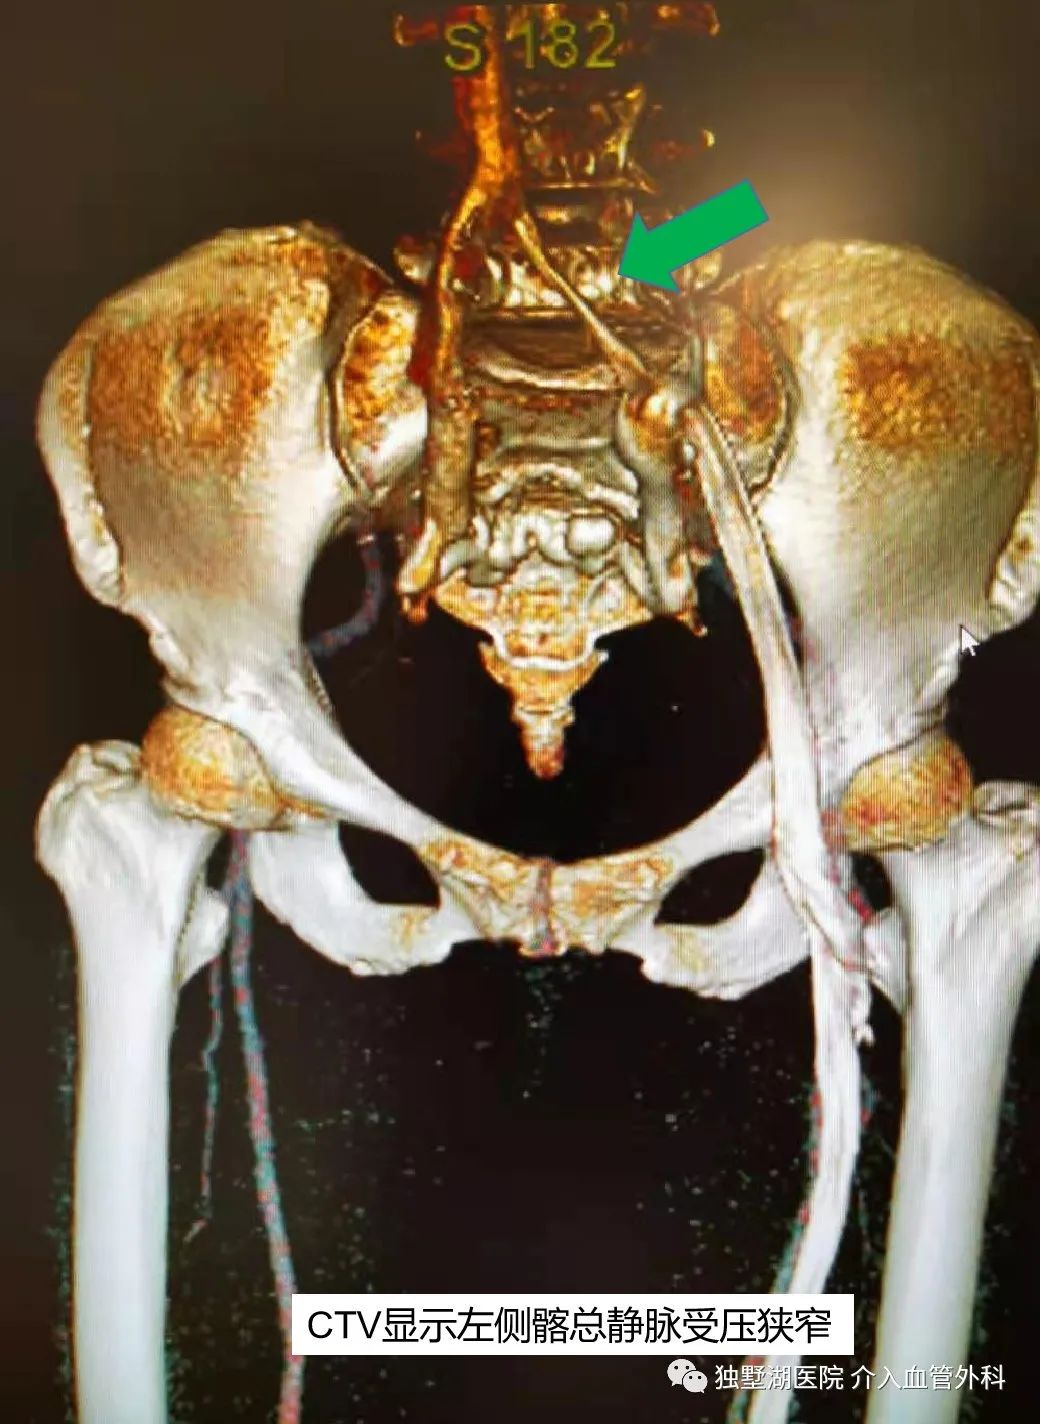

李阿婆,现年65岁,她受左下肢静脉曲张困扰有十余年,并且最近一年出现左下肢活动后水肿的症状。患者来我院就诊,张喜成主任接诊患者后,考虑患者静脉曲张,但有左侧髂静脉受压可能性。在放射科张卫国主任的指导下,该患者很快接受了CT下肢静脉造影检查。CTV图片清晰显示了李阿婆左侧髂静脉有明显受压。所以该患者的诊断明确为:左侧髂静脉压迫综合症伴有左下肢浅静脉曲张。